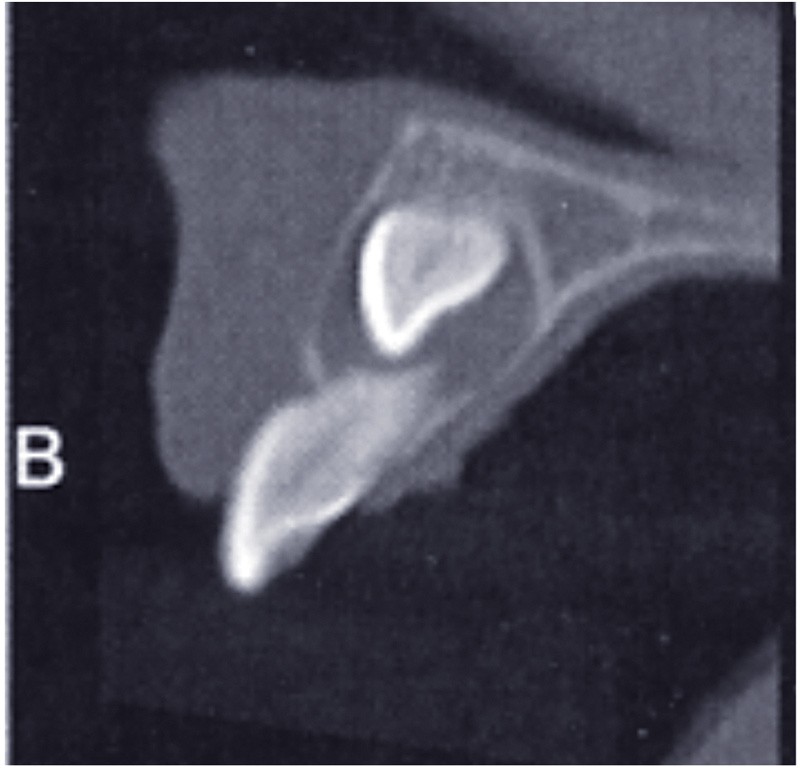

On observe un kyste péricoronaire sur 23 (fig. 2a).

La couronne de 23 est haute et discrètement vestibulaire par rapport à la racine de 21, partiellement résorbée.